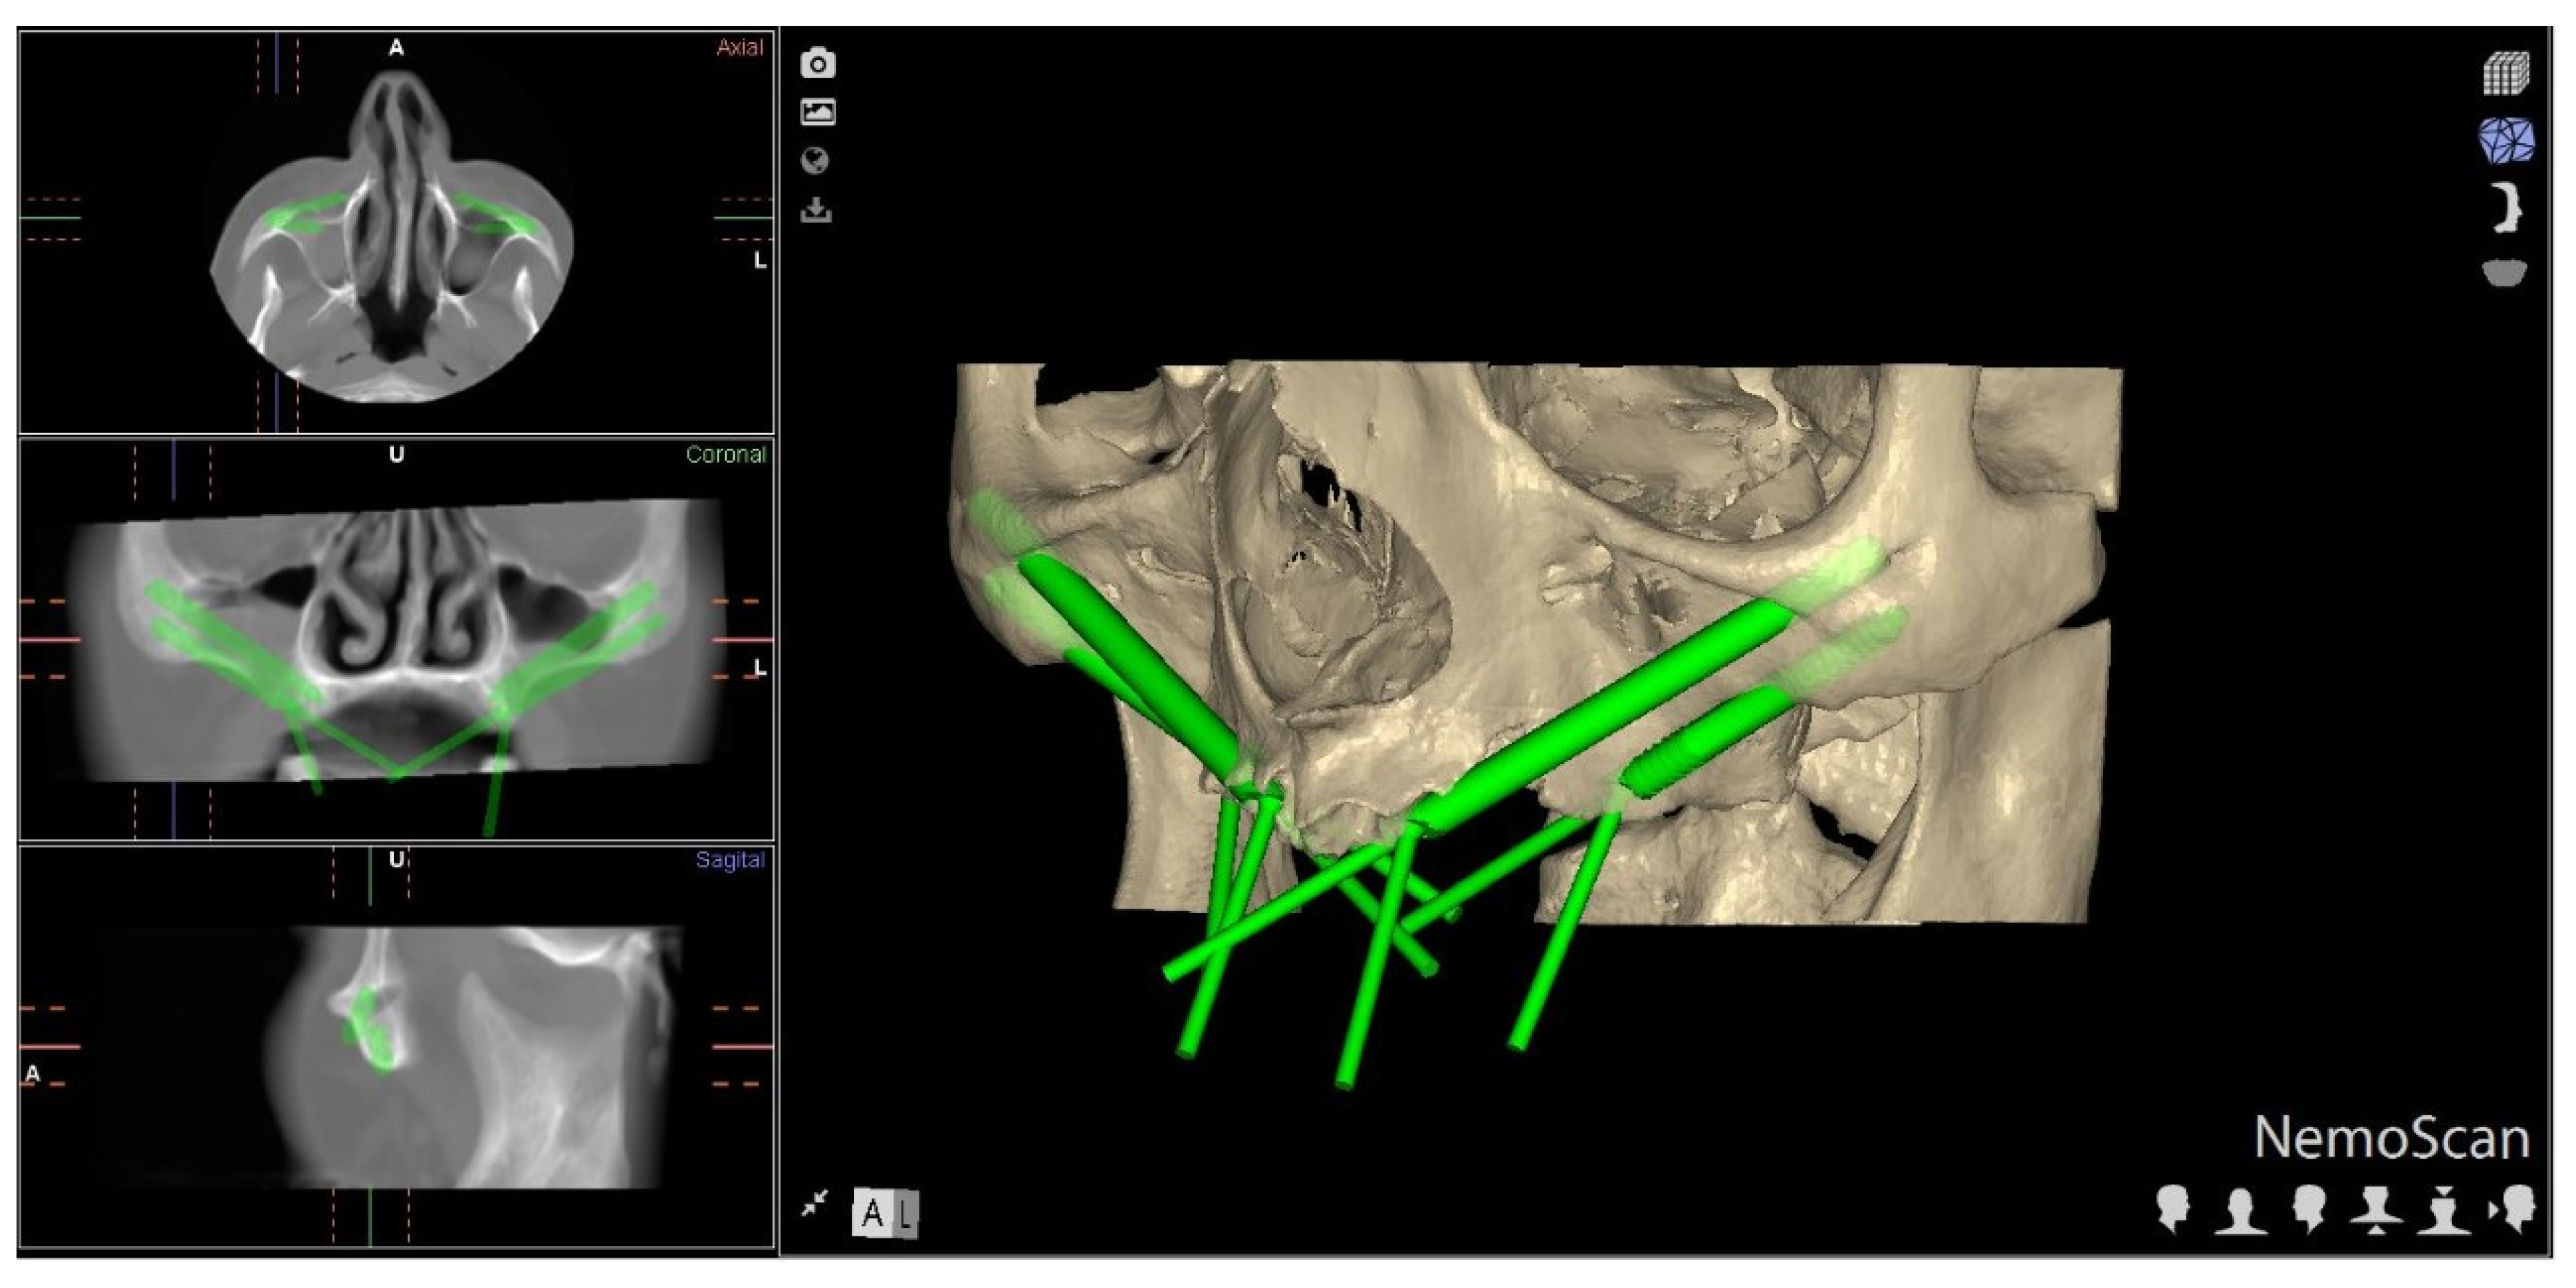

2.2. Experimental Procedure

2.3. Measurement Procedure